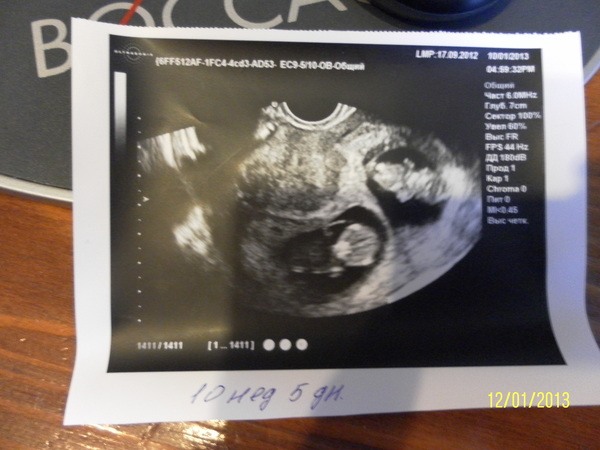

10 неделя беременности. Развитие плода. УЗИ в 3D. Как выглядит ребенок на 10 неделе

Десятая Неделя Беременности. Двенадцатая Акушерская Неделя.